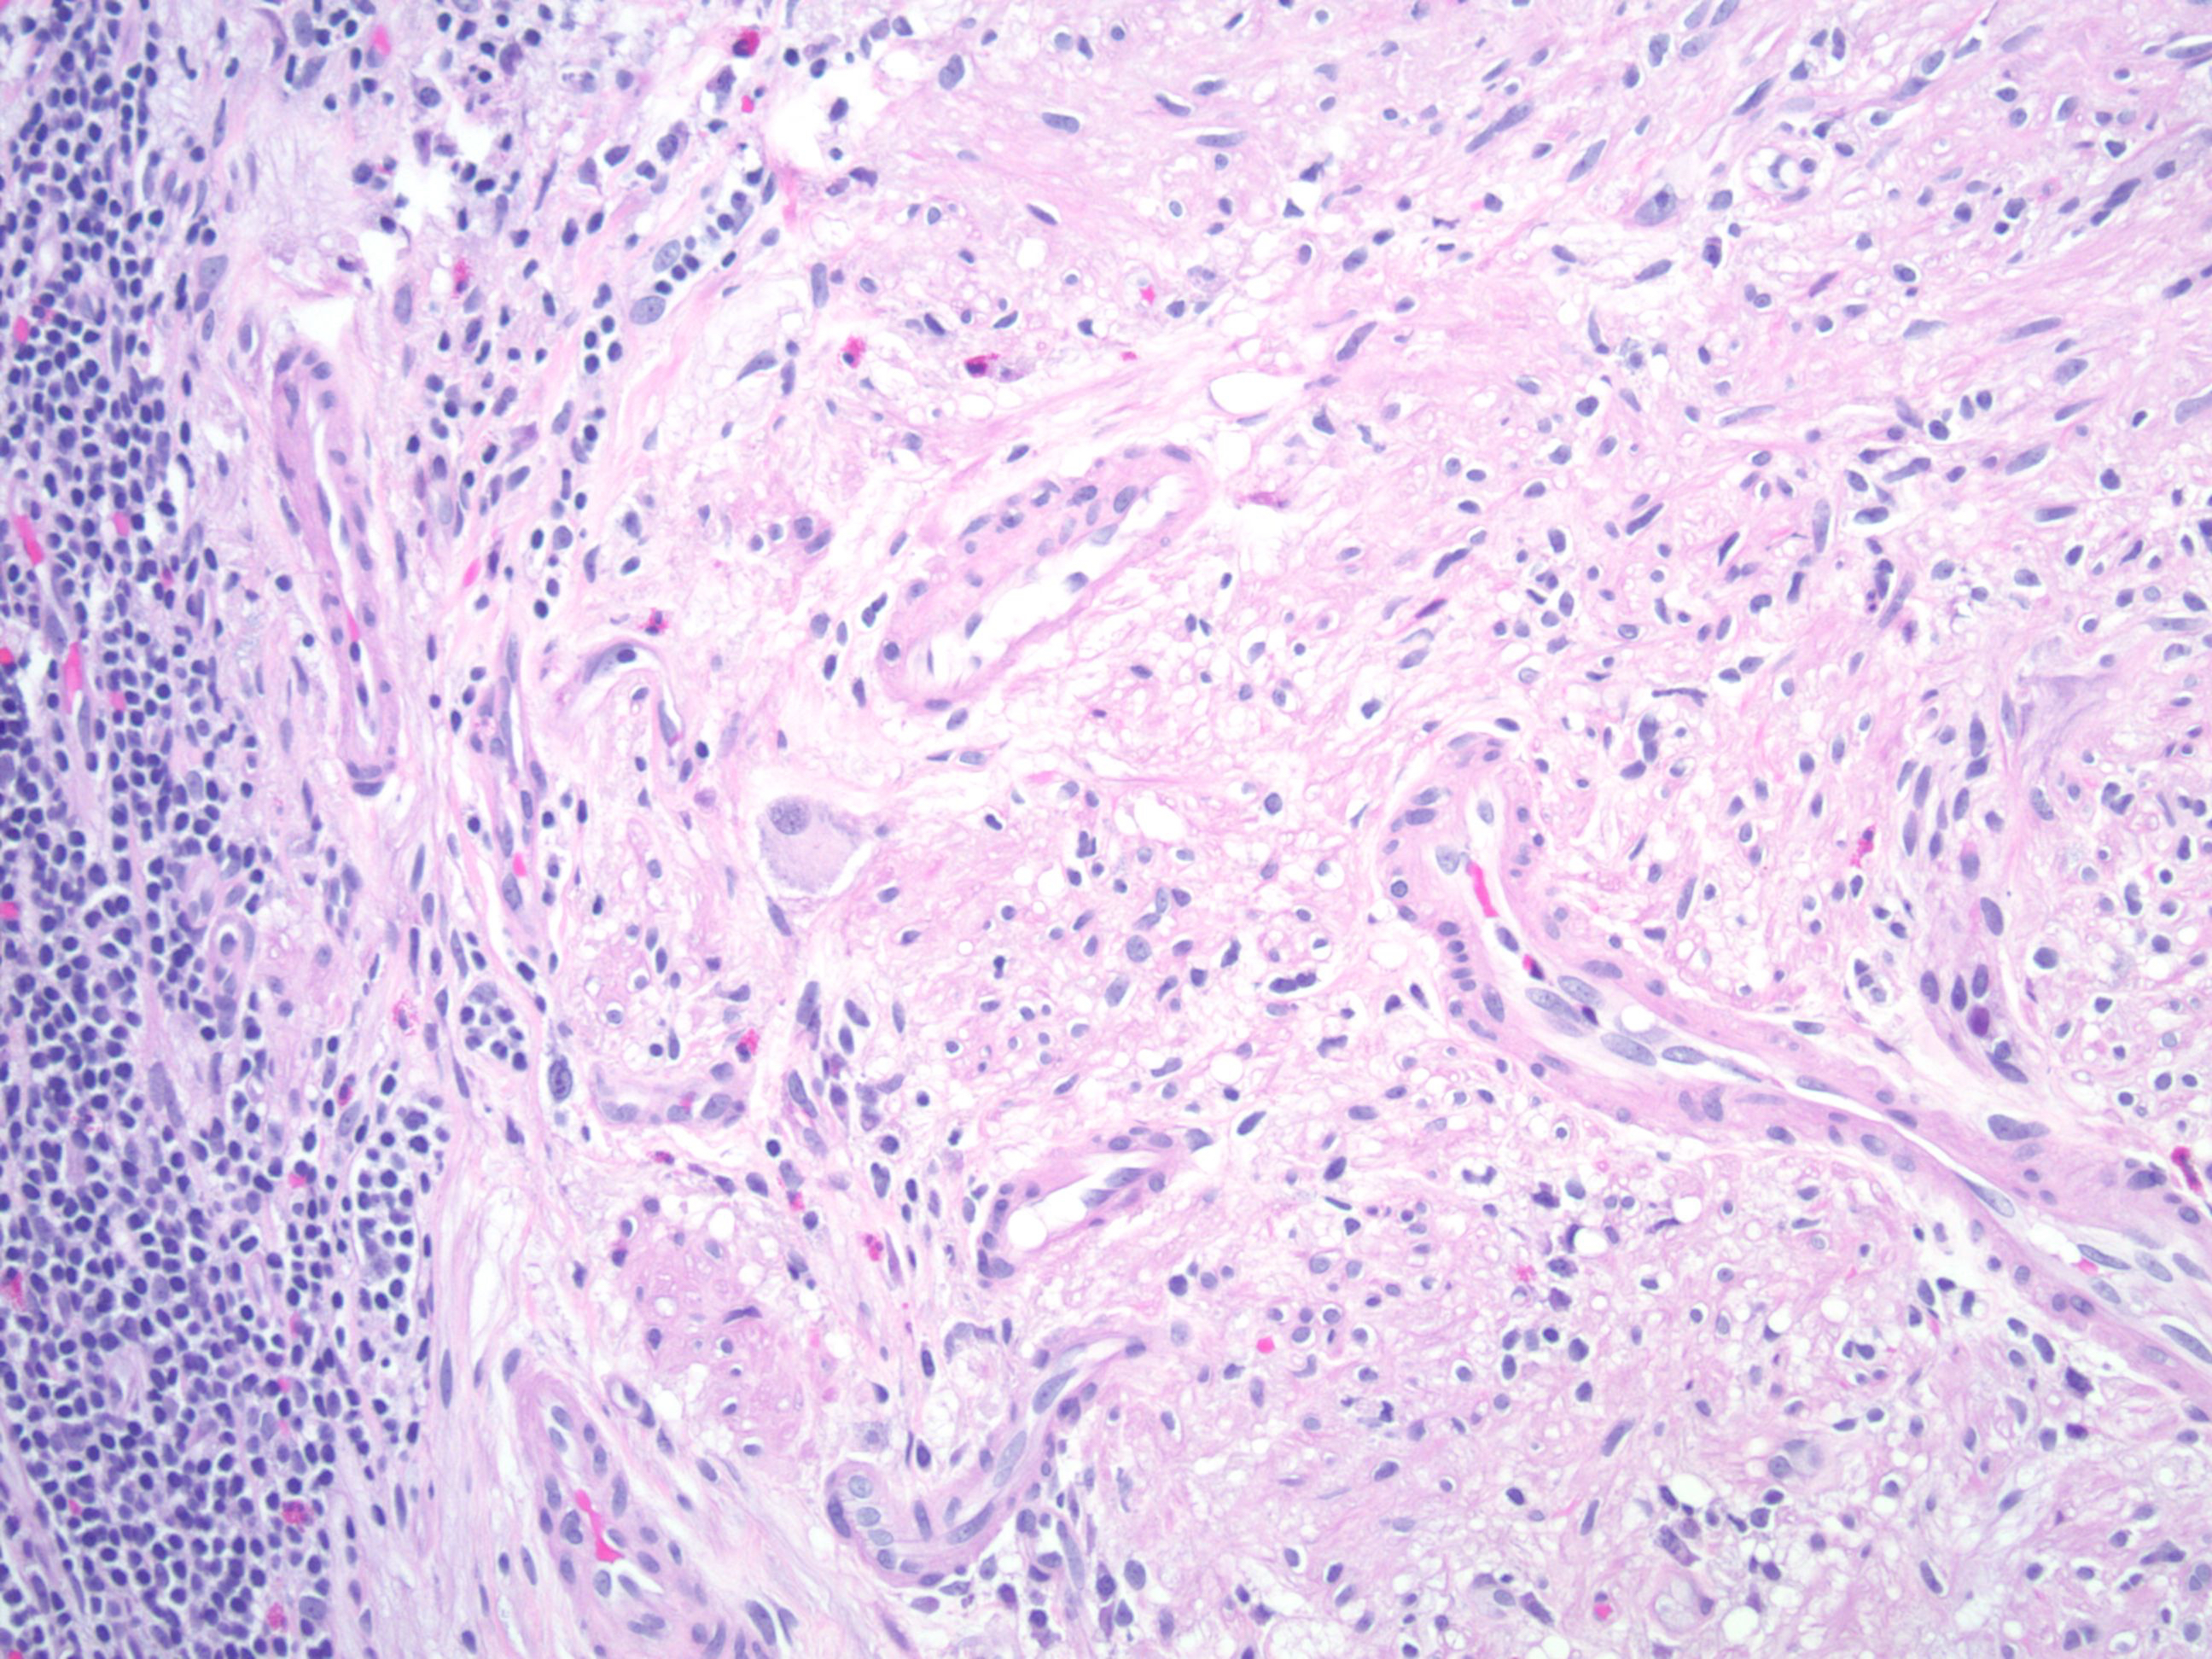

组织上显示伴散在神经节细胞的梭形细胞肿瘤,弥漫性节细胞神经瘤病主要集中在神经丛的周围,通常可延伸至固有层,胞浆稀少的梭形细胞伴散在的胶原,梭形细胞 S100 阳性,神经节细胞 synaptophysin 阳性。